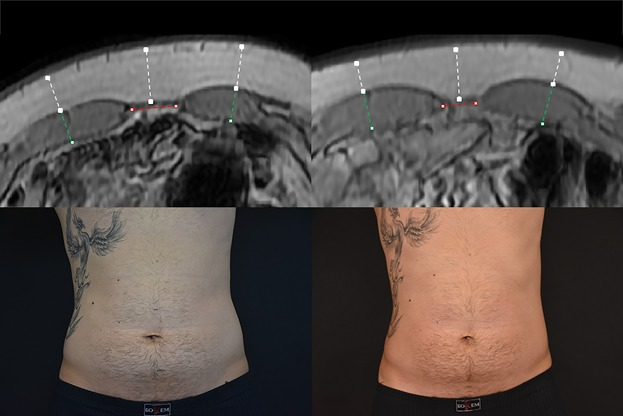

MRI‑Verified Muscle Hypertrophy

Published imaging studies using high‑intensity electromagnetic stimulation have demonstrated measurable increases in muscle thickness on MRI after a treatment series. These findings confirm that the contractions produced by HIEMT can stimulate true hypertrophy in targeted muscle groups.

left pre treatment / right 2 month follow up

(non edited medical journal photo)